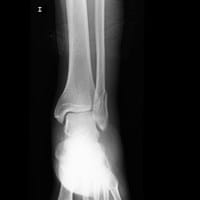

Huesos y articulaciones

Tiempo de recuperación maléolo externo